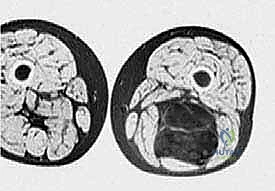

1. التصوير بالرنين المغناطيسي (MRI)

يُعد الرنين المغناطيسي بالصبغة المعيار الذهبي (Gold Standard) لتشخيص أورام الأنسجة الرخوة. يوفر صوراً ثلاثية الأبعاد وعالية الدقة تفصل الورم عن العضلات السليمة، وتوضح بدقة متناهية علاقة الورم بالعصب الوركي والأوعية الدموية الرئيسية (الشريان والوريد الفخذي العميق).